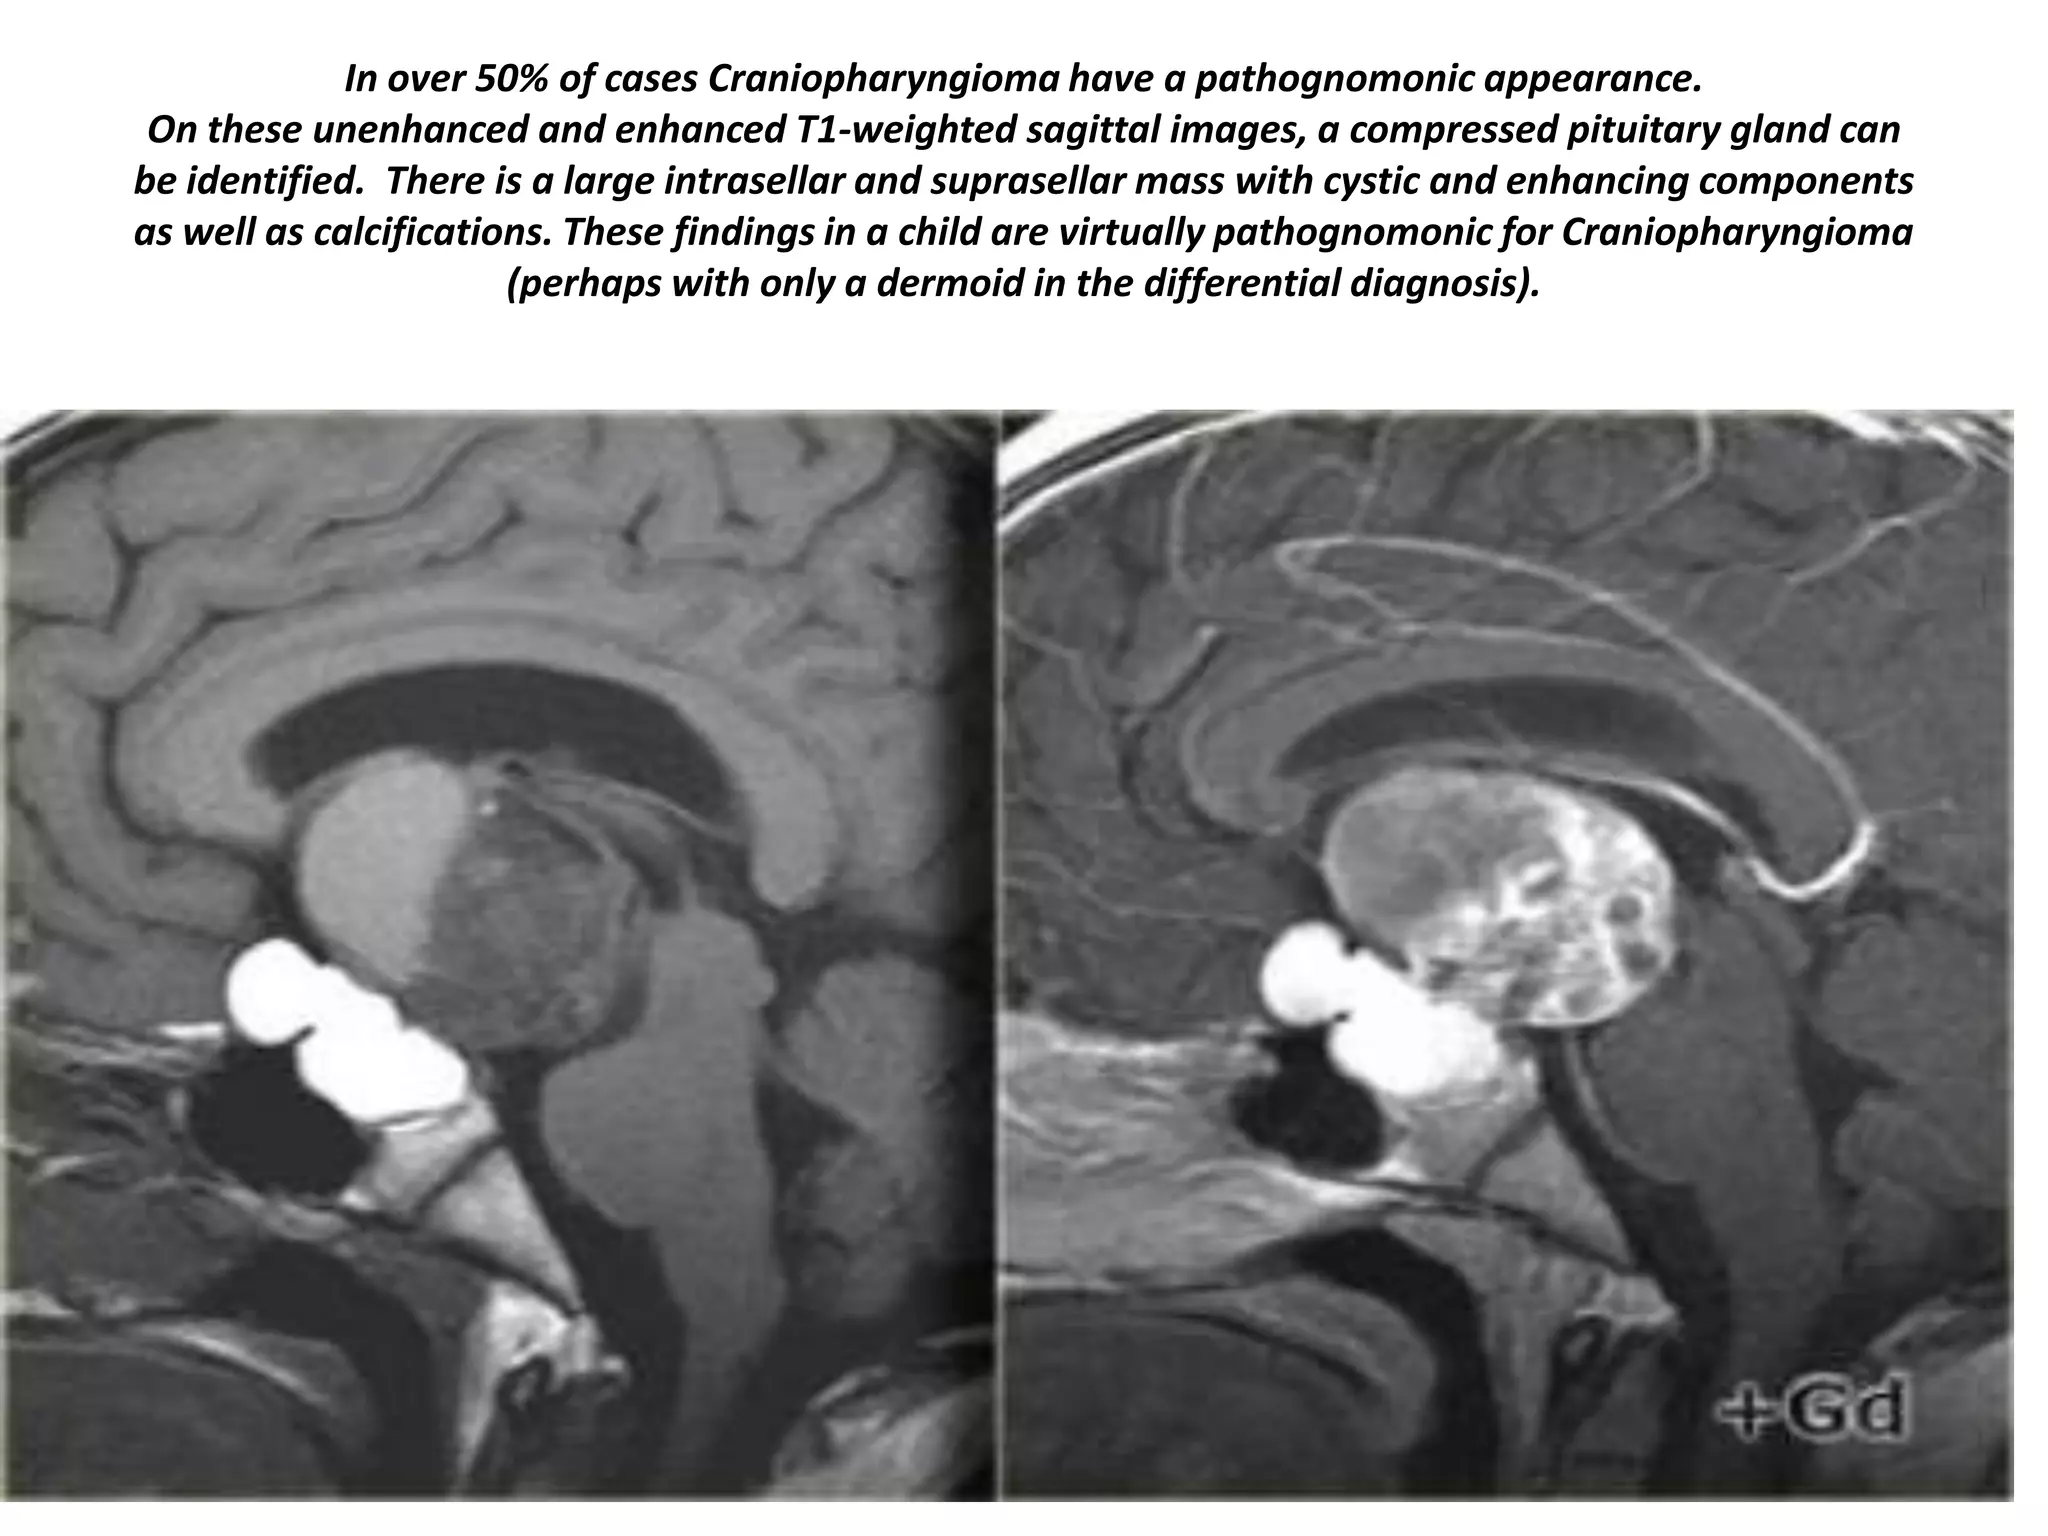

In over 50% of cases Craniopharyngioma have a pathognomonic appearance.

On these unenhanced and enhanced T1-weighted sagittal images, a compressed pituitary gland can

be identified. There is a large intrasellar and suprasellar mass with cystic and enhancing components

as well as calcifications. These findings in a child are virtually pathognomonic for Craniopharyngioma

(perhaps with only a dermoid in the differential diagnosis).